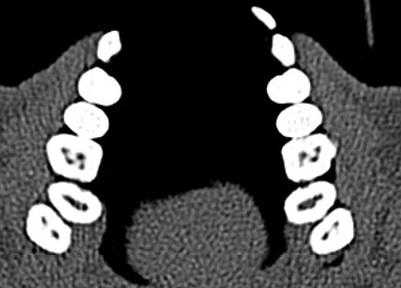

Ramamurthy и Matherene описывают ограниченность 2D изображений для определения MB2 каналов (Фото 1).

Фото 1: изображение MB2 в обоих первых молярах

Исследование, проведенное Neelkantan среди индийской популяции, обнаружило, что MB2 канал наиболее типичен для первого верхнего моляра по сравнению со вторым. Также IV анатомический тип канала встречается чаще, чем в монголоидной популяции.

Baratto Filho исследовали внутреннюю морфологию удаленных первых моляров верхней челюсти, сравнивая с данными, полученными при осмотре в микроскоп и при получении изображений КЛКТ ex vivo. Отчеты показали наличие 4-х каналов в 67,14% зубов и дополнительные корневые каналы в 92,85 % случаев в мезиобуккальном корне. Клиническая оценка показала слегка сниженный общий показатель (53,26%), но повышенный показатель выявления MB2 (95,63%), в то время как применение КЛКТ показало 37,05%. Ученые сделали вывод, что КЛКТ является хорошим методом для начальной оценки внутренней морфологии первого верхнего моляр, но для выявления устьев самым оптимальным способом является применение микроскопа. КЛКТ также применялся для выявления высокой встречаемости дистолингвального канала у Тайванцев, выявления аномалий в системе корневых каналов нижних премоляров, и помощи в выявлении искривлении корня (Фото 2).

Фото 2: Аксиальное изображение каналов C-формы во вторых молярах